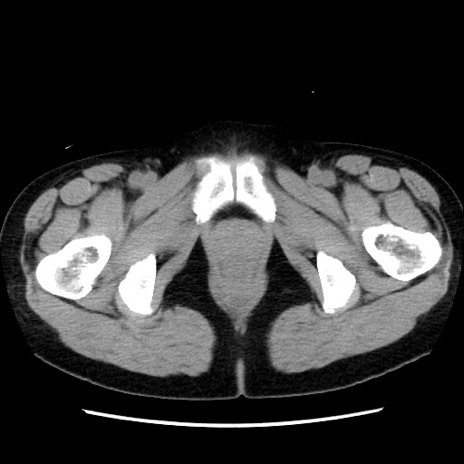

症例10(横断像)

【症例】 50歳代女性

【主訴】 腹痛

【現病歴】前日生レバーを食べた。今朝に排便あり。 昼前に突然発症の腹痛を生じ、当院救急外来を受診した。

【既往歴】 子宮筋腫にてで子宮全摘後

【身体所見】 意識清明、腹部:平坦、軟、下腹部やや左を中心に圧痛・反跳痛あり、筋性防御あり

【データ】WBC 7800、CRP 0.07